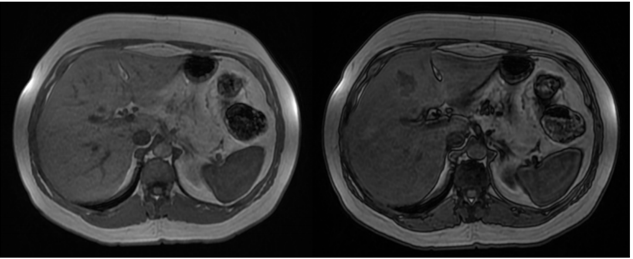

Mulher de 45 anos, sem história pessoal de câncer, foi submetida a exame de ressonância magnética do abdome superior com contraste venoso hepatoespecífico após achado de nódulo hepático incidental em ultrassonografia. Nas sequências pré-contraste, o nódulo apresentava discreto baixo sinal na ponderação T1 e discreto alto sinal na ponderação T2, ambas com supressão de gordura. Abaixo temos imagens nas sequências T1 em fase, T1 fora de fase, T1 pós-contraste (fase arterial) e T1 pós-contraste (fase hepatobiliar). As sequências pós-contraste mostram que o nódulo apresenta intenso realce arterial e hipossinal em relação ao parênquima na fase hepatobiliar.

Diante do exposto acima, analise as afirmativas abaixo e assinale a alternativa correta.

I. Há queda de sinal na ponderação T1 fora de fase tanto no parênquima hepático como no nódulo do segmento IV hepático em relação à ponderação T1 em fase, sugerindo quantidade significativa de gordura intracelular no parênquima e no nódulo.

II. O nódulo do segmento IV hepático tem características compatíveis com hiperplasia nodular focal.

III. O nódulo do segmento IV hepático tem características compatíveis com adenoma esteatótico.

IV. O meio de contraste hepatoespecífico auxilia no diagnóstico diferencial entre hiperplasia nodular focal e adenoma, uma vez que a hiperplasia nodular focal não capta contraste significativamente ou exibe apenas halo captante na fase hepatobiliar, enquanto o adenoma apresenta realce igual ou maior que o do parênquima hepático na mesma fase.